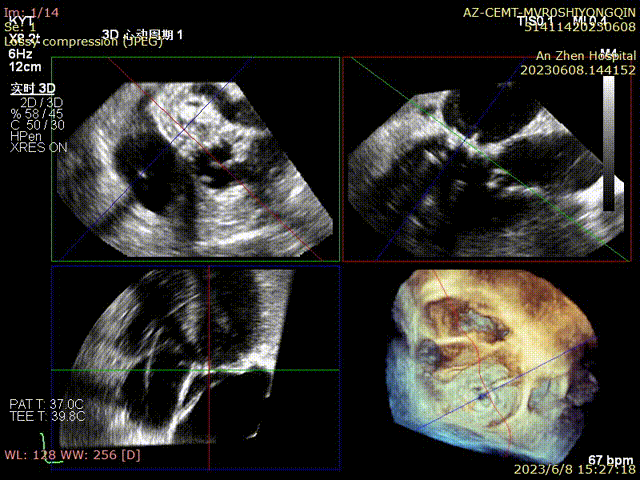

术前食管超声检查确认人工二尖瓣衰败,重度关闭不全

术后超声评估无反流